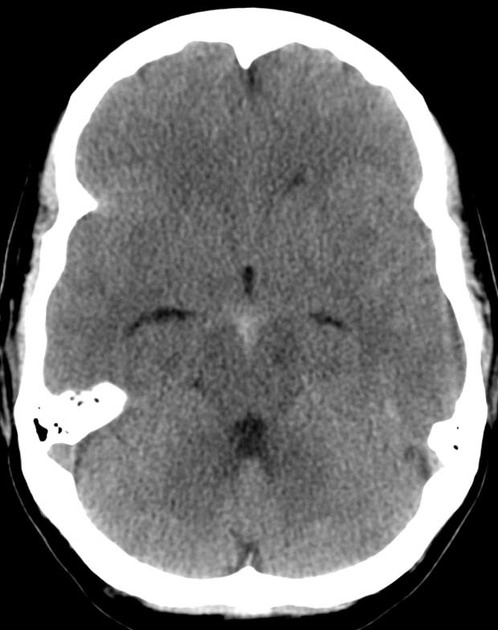

• Xuất huyết dưới nhện do vỡ phình mạch (Aneurysmal Subarachnoid Hemorrhage - aSAH)